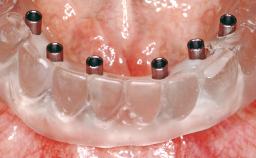

Immediate Loading of Eight Implants in the Maxilla and Six Implants in the Mandible and Final Restoration with Three-Unit and Four-Unit FDPs

Extensive scientific evidence has confirmed that immediately loaded implants with fixed full-arch provisional restorations can osseointegrate with success rates similar to conventionally or delayed loaded implants. A number of immediate-provisionalization techniques for edentulous jaws have been described. Some protocols differ when it comes to prefabricated provisional templates versus complete denture conversion; intrasurgical impressions versus direct relining; and cemented versus screw-retained provisional restorations. In this context, complete-denture conversion has been proposed for either intrasurgical impressions or direct relining. Another possibility is the utilization of a prefabricated provisional to be adapted either in the mouth (by direct relining) or in the laboratory (on a working model obtained from an intrasurgical impression).

Defining Characteristics Fully edentulous upper jaw to be rehabilitated with four or more implants

Modality 6+ implants with immediate loading

Defining Characteristics Fully edentulous upper jaw to be rehabilitated with an implant-borne fixed dental prosthesis

Loading Protocol Immediate